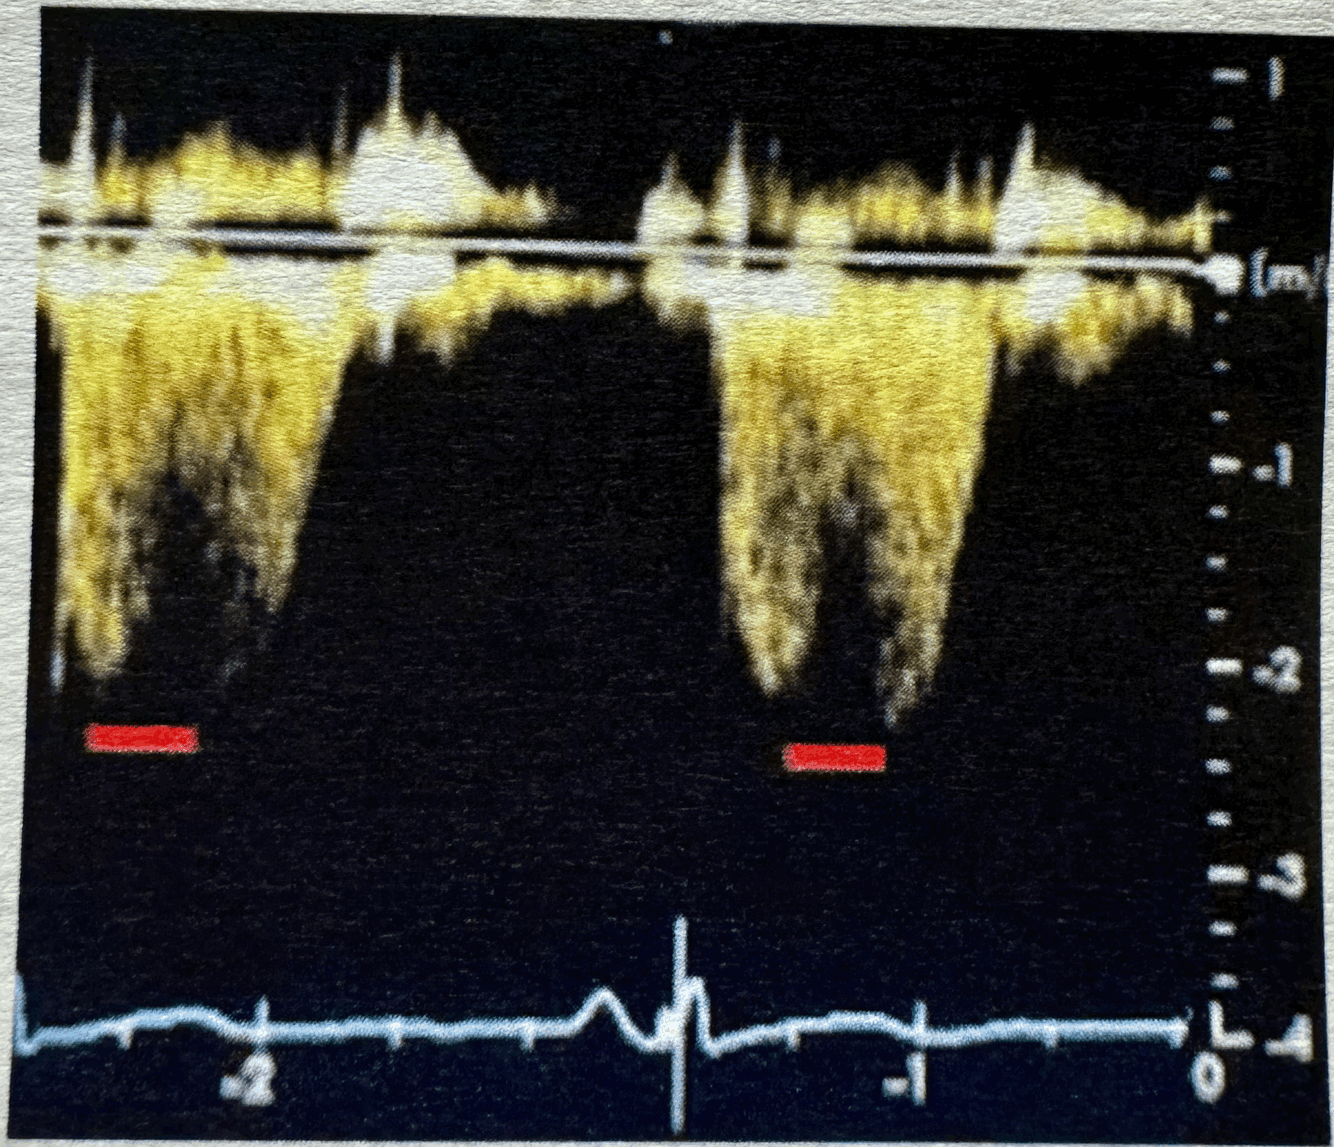

Q

What normal flow pattern is this and in what view?

A

descending AO Thoracic, SSN/Subcostal

How well did you know this?

1

Not at all